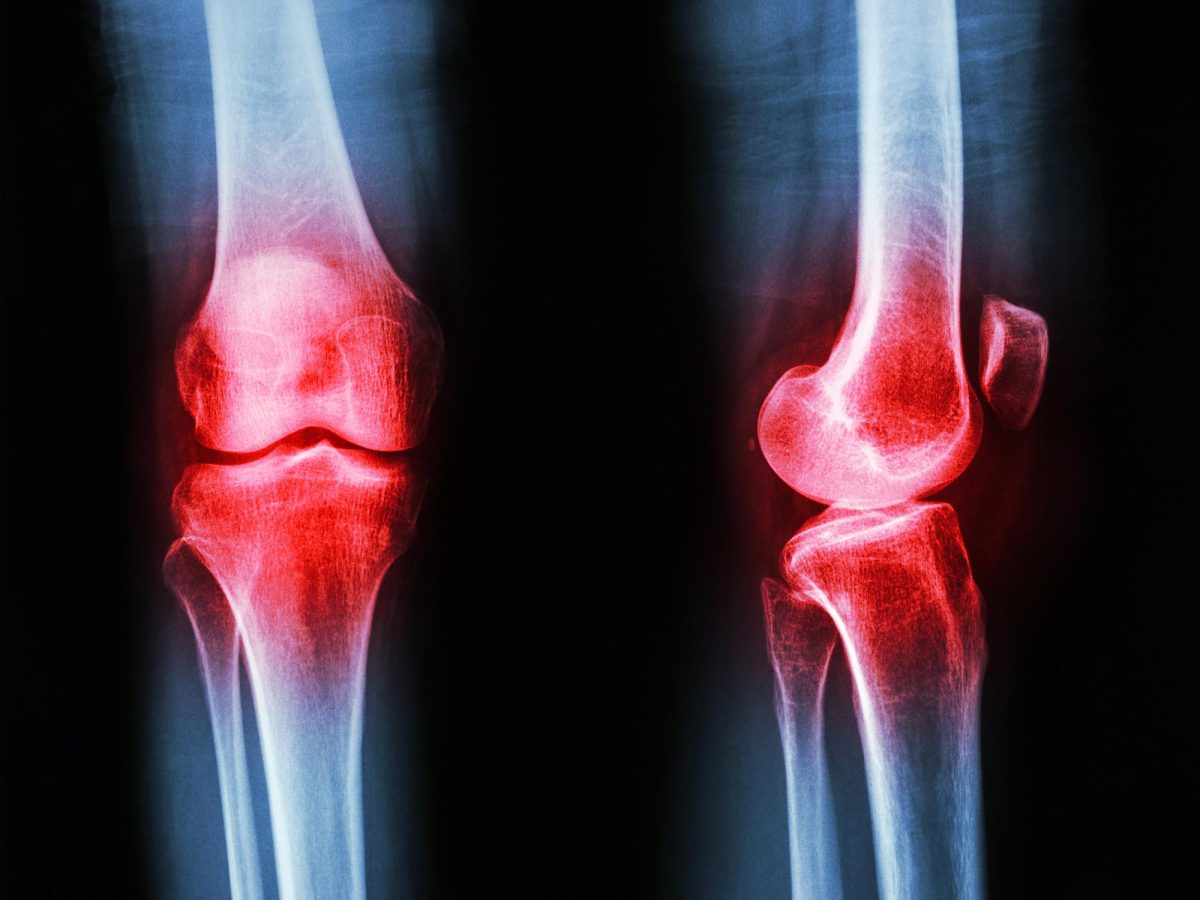

Osteoarthritis affects nearly one in four adults over 40 and is a significant cause of disability. This degenerative condition gradually erodes joint cartilage, and unfortunately, there aren’t existing methods to reverse this damage. Current treatments primarily focus on pain relief with medications, eventually leading to joint replacement.

Supported by the National Institutes of Health and other agencies, the study focused on patients suffering from mild to moderate osteoarthritis, particularly in the inner compartment of the knee. The best way to reduce stress on this area can differ from person to person, based on their natural walking styles.